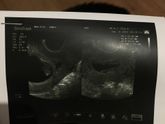

Девочки а можно врача попррсить снизит дозу утрика до 100 просто мне его при маленькой гематомке прописали вот уже 12 неделя почти , все хорошо ничего не болит , мне назначили 1 раз на ночь по 200 мг , были роды сыра родила 2017 все было прекрасно и … Читать далее